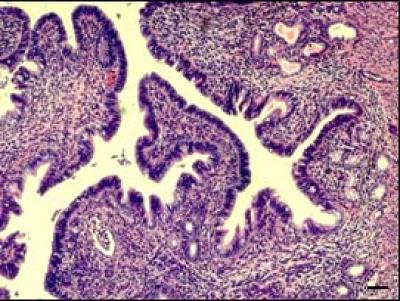

Published in the Feb. 3 early online issue of EMBO Molecular Medicine , the study explored an inherited mutation located in part of the KRAS gene, which leads to abnormal endometrial growth and endometrial risk. In endometriosis, uterine tissue grows in other parts of the body, such as the abdominal cavity, ovaries, vagina, and cervix. The condition is often hereditary and is found in 5%-15% of women of reproductive age, affecting over 70 million women worldwide.